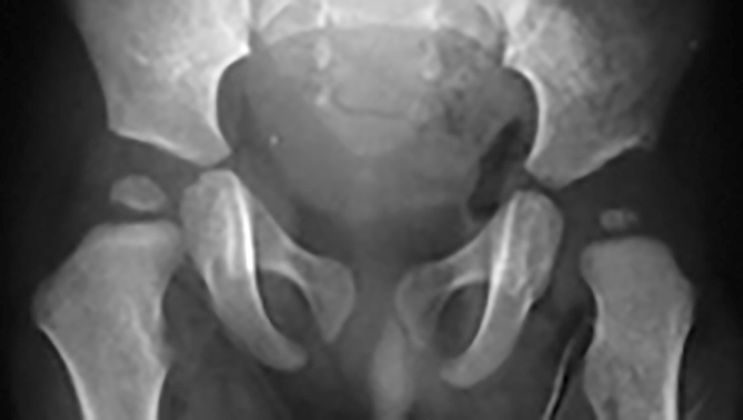

L’esame ecografico è stato introdotto negli anni 80 da Graf che ha proposto una classificazione in quattro tipi per valutare condizioni di immaturità dell’anca (Tipo II) e condizioni più gravi come la sublussazione (Tipo III) e la lussazione franca (Tipo IV) 5. Il metodo è basato sulla valutazione dell’entità di due angoli: l’angolo α formato dalla linea di base che è rappresentata dalla continuazione verso il basso del profilo laterale dell’ala iliaca e la linea del tetto osseo mentre l’angolo β è formato sempre dalla linea di base e la linea del tetto cartilagineo. La radiografia dell’anca può essere attualmente utilizzata con lo scopo di confermare la diagnosi dopo i 4-6 mesi di vita. Nei casi di displasia è presente la caratteristica triade di Putti caratterizzata dalla sfuggenza del tetto acetabolare, dal ritardo di comparsa o dall’ipoplasia del nucleo di ossificazione della testa femorale che rappresentano segni di ritardo dell’ossificazione acetabolare e dall’allontanamento/risalita dell’epifisi prossimale del femore che viene valutata attraverso interruzione dell’ogiva o arco di Shenton. Tale ogiva è formata dal margine mediale della metafisi femorale che, in condizioni di normalità, si continua con il margine inferiore della branca ileo-pubica (Fig. 5).

Gli ostacoli alla riduzione sono generalmente rappresentati dalle retrazioni muscolo-tendinee degli adduttori e dello psoas iliaco, i cui tendini vengono sezionati, dal restringimento della capsula articolare che viene incisa, dall’ipertrofia del legamento rotondo e del pulvinar e, in alcuni casi, del legamento trasverso che vengono rimossi. La riduzione cruenta può essere eseguita utilizzando una via di accesso mediale o antero-laterale con i medesimi risultati nei pazienti fino a tre anni di età (Figg. 7-8) 9.

Nei casi di lussazioni inveterate, si preferisce l’accesso antero-laterale e potrebbero essere necessarie eventuali osteotomie del bacino e/o dell’estremo prossimale del femore. Tali osteotomie tuttavia, vengono anche utilizzate quando con la riduzione cruenta non si ottiene una soddisfacente copertura della testa del femore.

Le osteotomie acetabolari hanno lo scopo di aumentare la copertura della testa del femore agendo sull’acetabolo. Queste osteotomie vengono generalmente suddivise in 2 gruppi: osteotomie di riorientamento (osteotomie di Salter, Dega, Pemberton, triplice osteotomia, osteotomia periacetabolare bernese) 10, e osteotomie di salvataggio che hanno lo scopo di stabilizzare l’anca, aumentando la copertura della testa femorale con una maggiore superficie di contatto (acetabuloplastica di Shelf, osteotomia di Chiari). Queste ultime osteotomie non preservano la cartilagine articolare nella speranza che si sviluppi una metaplasia cartilaginea che sostituisca la cartilagine articolare originaria. Le osteotomie femorali hanno lo scopo principale di correggere la coxa valga antiversa, riorientando la testa del femore attraverso una derotazione e una varizzazione dell’estremo prossimale dell’osso; tuttavia, nei casi più gravi, per ottenere la riduzione può essere necessario associare un accorciamento del segmento scheletrico.